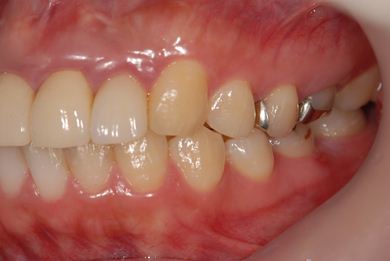

治療前

• 治療前